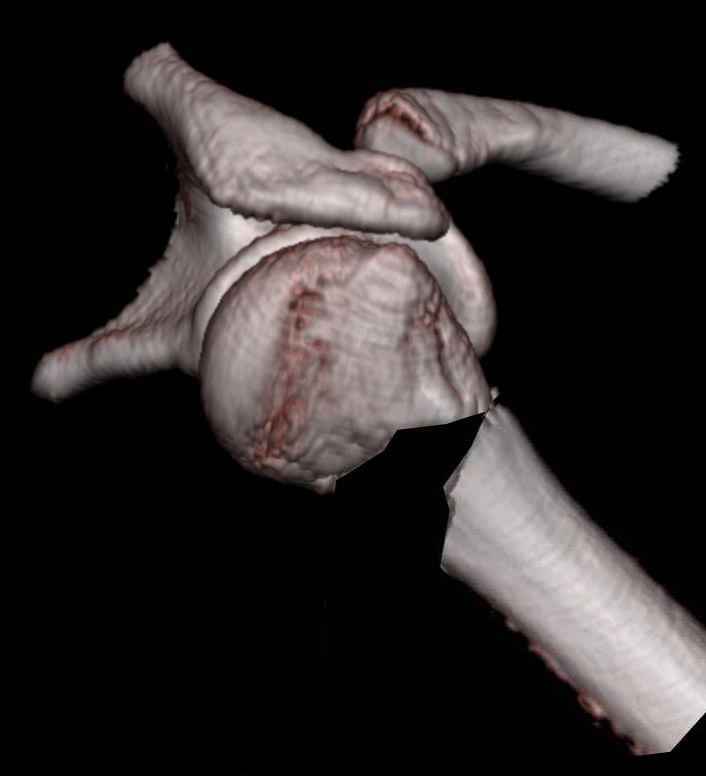

У нас это называется "по Мительману". КТ, да еще и возможность трехмерной реконструкции делает картину повреждения значительно более наглядной.

Эта "репозиция" сделана только на картинке, чтобы было видно, как основные фрагменты должны располагаться после восстановления взаимоотношений головки и диафиза. Понятно, такого диастаза не будет, поскольку есть внедрившаяся в головку медиальная стенка дистального отломка.

Последняя картинка сделана, чтобы более наглядно оценить тот угол, на который смещены отломки.